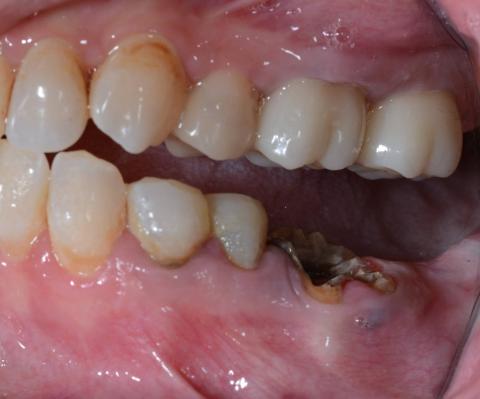

Severely Decayed Root Stump With Advanced Infection Causing Persistent Oral Odor

Zoom 100% Clinical Examination – What We See

Lower posterior region (missing crown with remaining root fragment)

Key findings from the image:

Severely broken-down tooth reduced to a root stump

Dark brown to black necrotic tooth structure

Accumulated plaque, calculus, and food debris

Surrounding gum tissue appears inflamed and irritated

Evidence of chronic bacterial infection

Open space allowing constant food impaction

Critical note:

The tooth crown is no longer present. Only decayed roots remain, acting as a permanent infection reservoir.

Primary Diagnosis

Non-Restorable Root Stump With Chronic Dental Infection